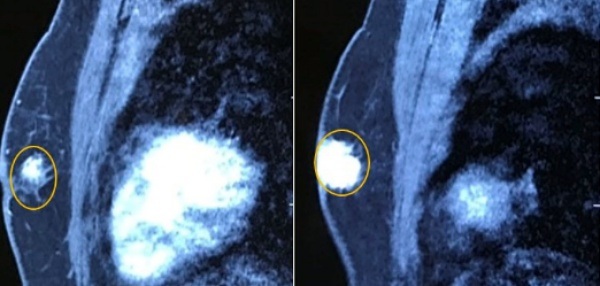

Tuyến vú trái có khối u kích thước 2×2,5cm, chắc, ranh giới không rõ, còn di động.

Người đàn ông mắc căn bệnh tưởng chỉ có ở phụ nữ - 1

Hình ảnh chụp cộng hưởng từ tuyến vú có khối u ngay dưới núm vú trái kích thước 21x28mm, chưa xâm lấn cơ thành ngực, co kéo núm vú (Ảnh: B.V).

Bệnh nhân được chỉ định cắt toàn bộ tuyến vú trái, vét hạch. Sau hậu phẫu bệnh nhân ổn định sẽ tiếp tục điều trị các liệu pháp toàn thân (hóa trị, nội tiết…) kết hợp với điều trị và theo dõi bệnh lý về tim mạch.